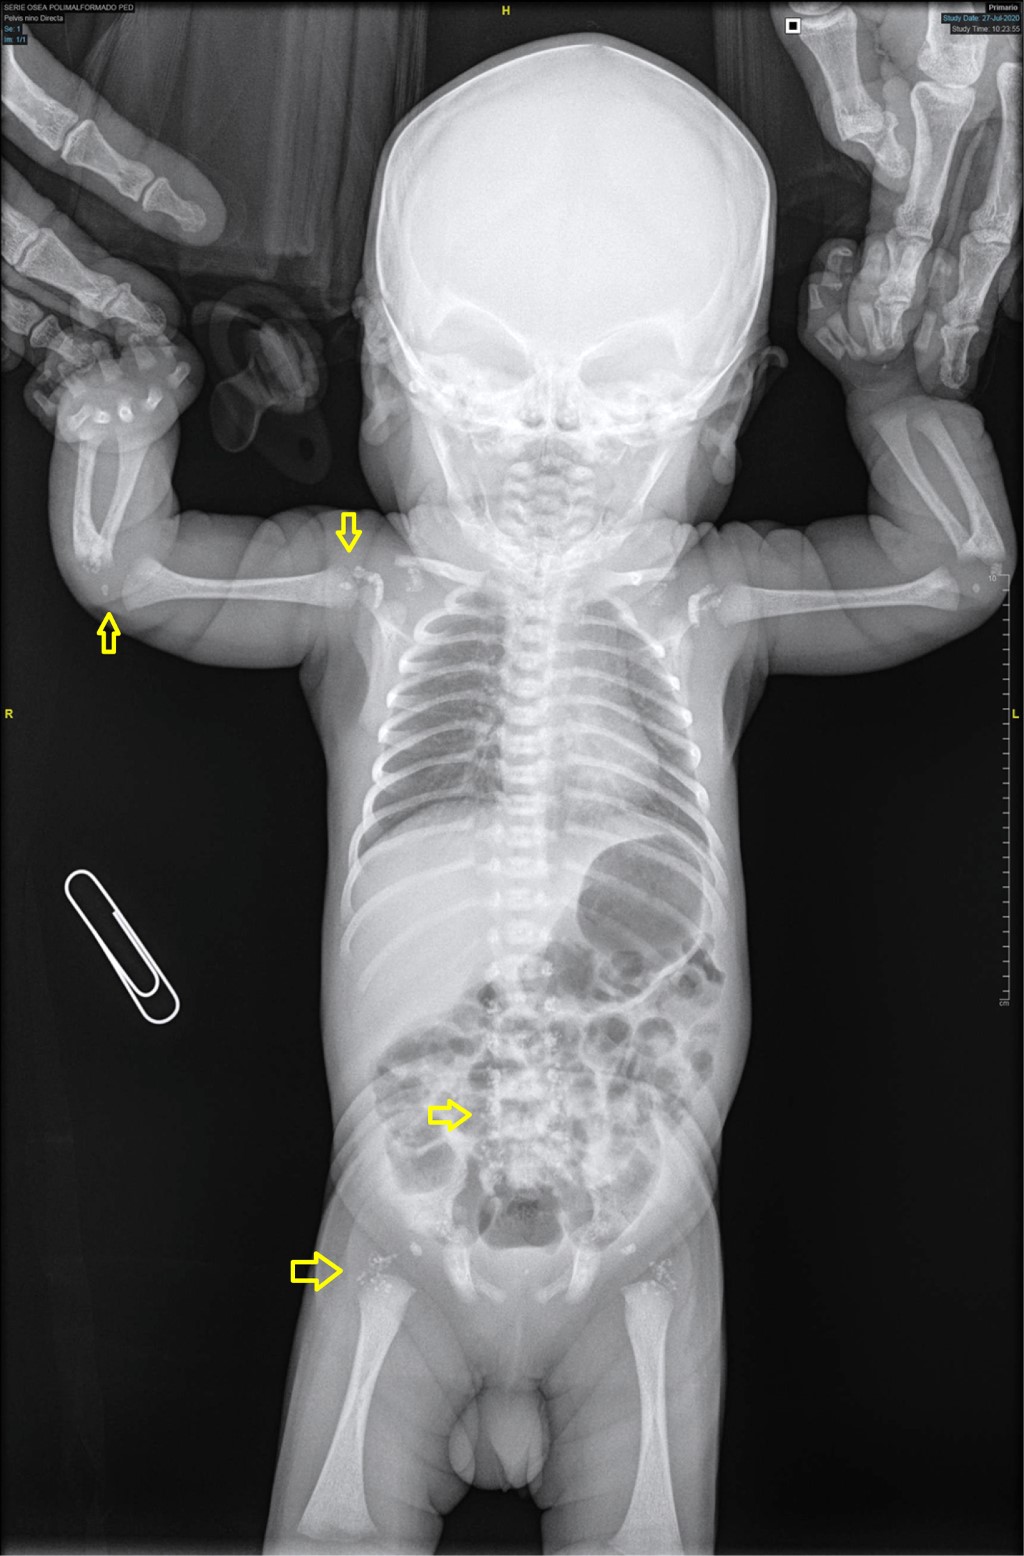

Chondrodysplasia punctata in neonate

We present the radiographic images of a newborn in whom a diagnosis of chondrodysplasia punctata was reached. Patients with this disorder have pinpoint calcifications in multiple joints.

Figure 2